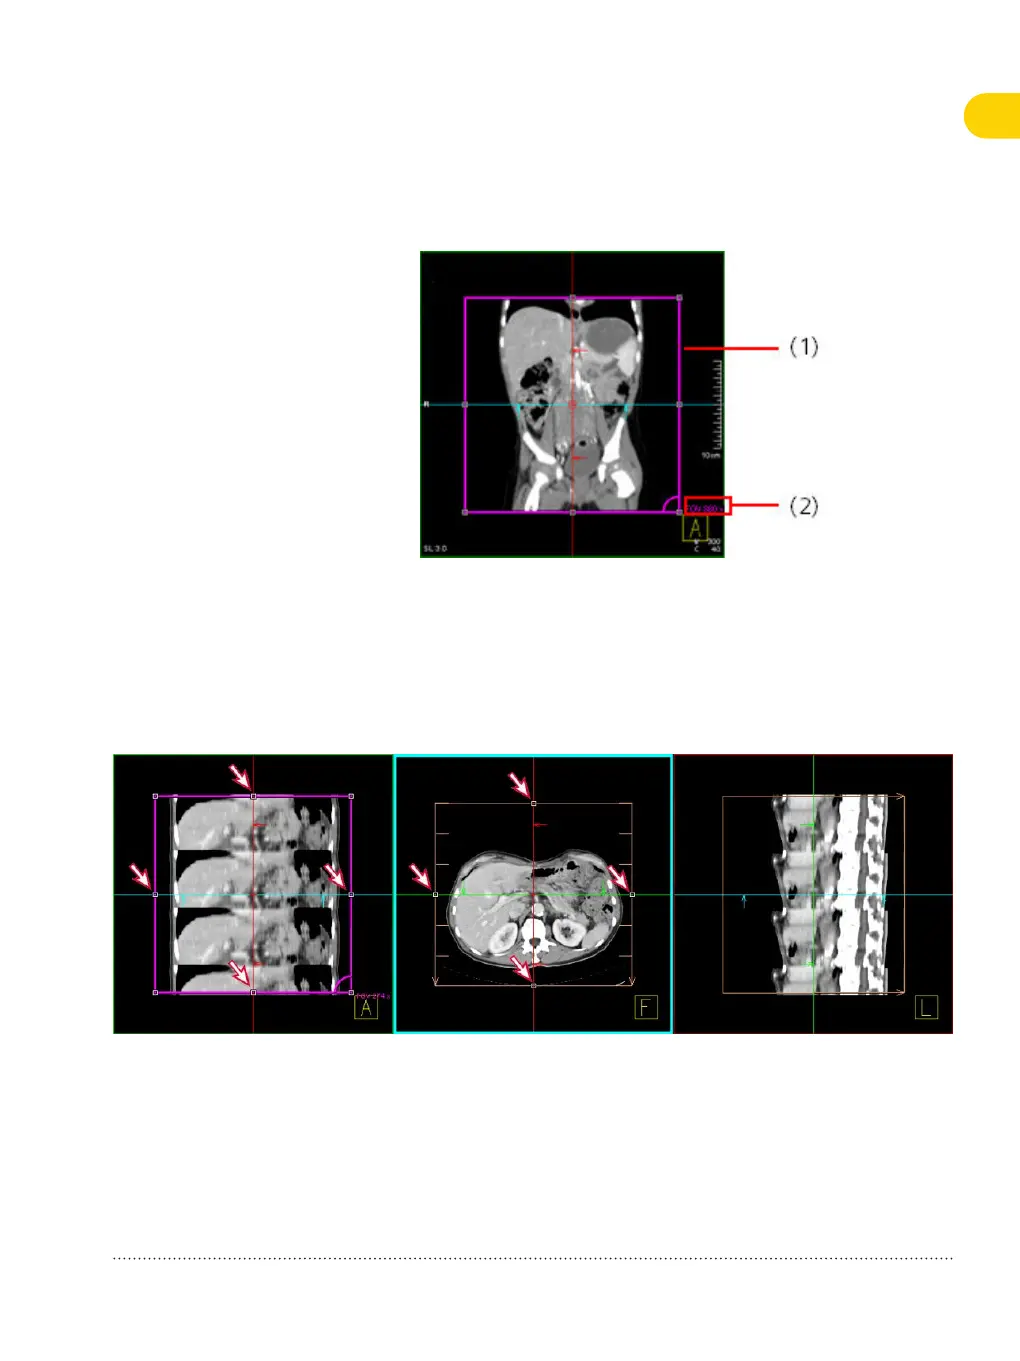

FoV segment (coronal view)

(1) FoV object

(2) FoV size

4 Adapt the recon range in the 3D recon segments by clicking and

dragging the handles that are displayed around the graphic range

objects.